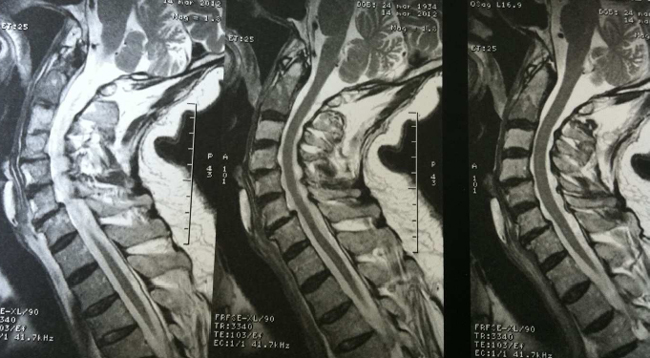

Au-dessus de T4

Dr Jacques Fechtenbaum Hôpital Cochin - Paris

Mr D. est né le 24 mars 1934. Il est suivi et traité pour un cancer des intestins et des métastases pulmonaires. Il vient vous consulter pour des cervicalgies hautes avec ébauche de névralgie d’Arnold.

Ces douleurs sont d’horaire inflammatoire. Vous évoquez le diagnostic de métastases osseuses et vous demandez d’emblée une IRM du rachis cervical.

L’IRM confirme le diagnostic de métastases ostéolytiques de C2 avec un hypersignal T2 rehaussé après